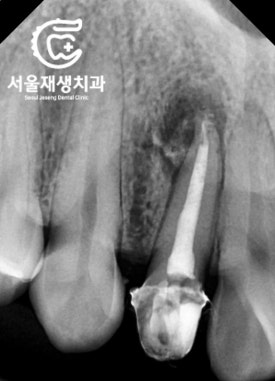

치료 전 후 엑스레이 사진입니다.

뿌리에 들어가는 기둥(포스트)를

다시 할 필요는 없다고 판단했습니다.

간단한 뿌리 충전과 (=신경치료)

간단한 머리 충전 (=레진충전) 및

크라운 치료로

모든 과정을 마무리했습니다.